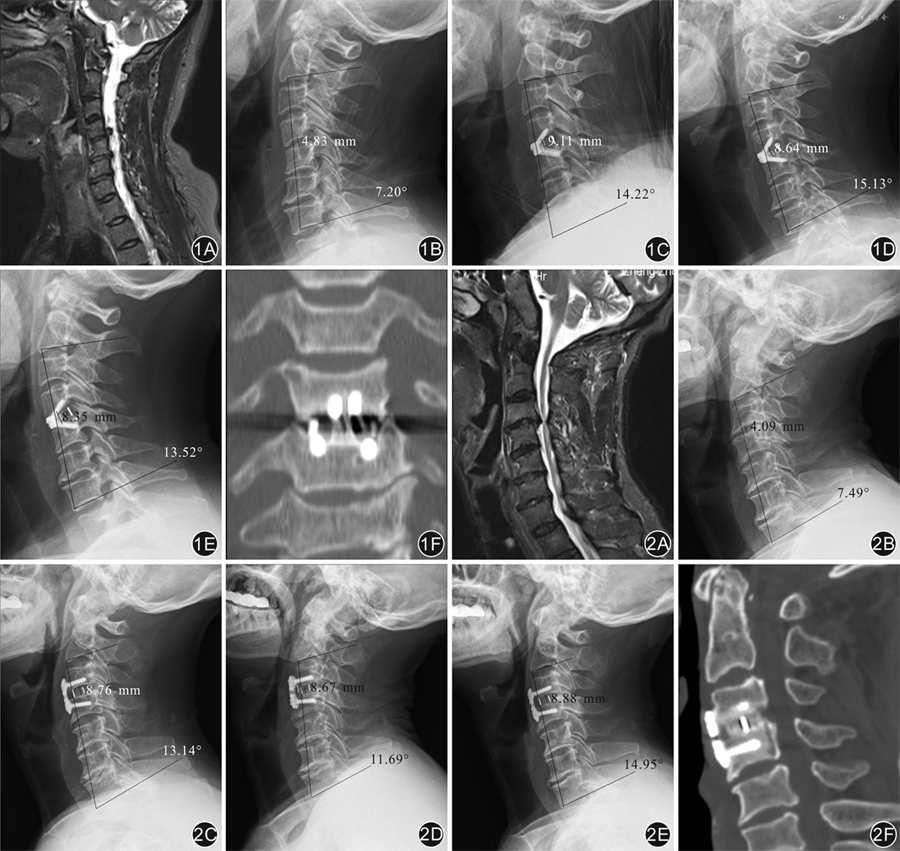

术后6个月时,2组患者均达到椎间植骨区骨性融合,融合率达100%。Zero-P组患者的Zero-P融合器未发生松动、滑脱或断裂,椎体未发生骨折,Cage组患者出现4例颈前路钛板松动。2组患者术后3个月及末次随访时,椎间隙高度及Cobb角均较术前明显改善,差异均有统计学意义(P值均<0.05);组间比较差异均无统计学意义(P值均>0.05)。见表3。

Zero-P组与Cage组单节段脊髓型颈椎病患者不同时间点椎间隙高度及颈椎生理曲度比较(±s)

| 观察时间 | 椎间隙高度(mm) | Cobb角(°) | |||||||

|---|---|---|---|---|---|---|---|---|---|

| Zero-P组 | Cage组 | t值 | P值 | Zero-P组 | Cage组 | t值 | P值 | ||

| 例数 | 16 | 16 | 16 | 16 | |||||

| 术前 | 3.9±0.8 | 3.7±0.9 | 0.49 | 0.628 | 9.8±2.3 | 9.8±2.3 | -0.05 | 0.961 | |

| 术后3个月 | 7.7±1.4a | 7.9±1.3a | -0.41 | 0.691 | 19.5±3.6a | 19.9±3.8a | -0.30 | 0.763 | |

| 末次随访 | 7.6±1.4a | 7.8±1.3a | -0.42 | 0.684 | 19.4±3.7a | 19.7±3.8a | -0.35 | 0.729 | |

| F值 | 36.76 | 49.10 | 32.59 | 33.38 | |||||

| P值 | <0.001 | <0.001 | <0.001 | <0.001 | |||||

注:Zero-P为零切迹颈前路椎间融合系统;a与术前比较,P<0.05

Pitzen等[8]研究指出,Zero-P是颈前路融合术理想的内固定材料,接受Zero-P治疗的患者椎间融合更快,置入物相关并发症更低,并能更好地维持颈椎的生理前凸,且这种优势在术后2年内更突出。在本组病例中,Zero-P组和Cage联合钛板组患者术后生理曲度均得到明显恢复,差异无统计学意义(P>0.05),与刘光普等[9]报道相似。由于生理前凸维持与置入物大小、位置、接触面积、术中撑开高度等多种因素有关,笔者认为,要对比2种术式对术后颈椎生理前凸维持的有效性,还需要大量的临床观察。Barbagallo等[7]指出,Zero-P融合器并不需要过分追求椎体前方的平整,在进行椎管减压后,仅需处理上下椎体的软骨板,相对于颈前路钛板,能显著降低手术时间。Yin等[10]也指出Zero-P融合器在手术减压后置入椎间隙不突出于颈椎序列,可简化传统的Cage联合钛板手术过程,迅速提高手术节段的稳定性。本研究的结果亦显示,Zero-P组的手术时间明显少于Cage联合钛板组,差异有统计学意义。Barbagallo等[7]发现,接受Zero-P融合器治疗的患者术后都有理想的矢状位序列,椎间融合率94.5%、神经减压满意,多节段手术患者未因为同一个椎体上有4个螺钉而发生骨折。研究证实,Zero-P有着与Cage联合钛板相似的生物力学稳定性[10, 11]。本研究中,2组病例术后JOA评分、SF-36评分、NDI评分及椎间隙高度及颈椎生理前凸(Cobb角)都较术前明显改善,而2组间差异均无统计学意义,术后椎间融合均达到100%。另外本研究中,Zero-P组患者的Zero-P融合器未发生松动、滑脱或断裂,而Cage联合钛板组患者出现4例颈前路钛板松动。